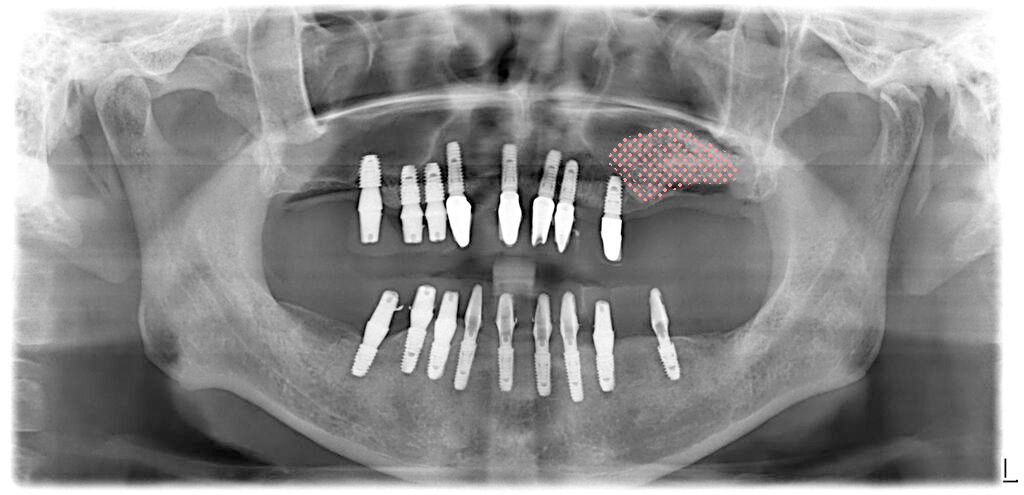

발치즉시임플란트 수술당일 임시치아

전체 치아를 모두 발치하고 임플란트를 식립했습니다. 우측 위쪽의 상악동부위에는 간단한 방식으로 거상술을 진행했습니다.(초록색)

그러나, 좌측 위 어금니 부위쪽 상악동은 이미 상악동이 뚫려 있어 우선 발치만 진행을 해 두었습니다.

그렇게 해서 모든 치아 발치, 염증제거, 위쪽에 8개, 아래 9개의 임플란트를 식립했습니다. 저는 임플란트를 넉넉하게 심는 편입니다. 그 이유는 아래에 링크를 걸어두겠습니다.

그리고 식립한 모든 임플란트에 지대주를 연결해서 수술당일 임시치아를 끼워드렸습니다.

그리고 다시 2개월 후 상악동 윈도우수술을 해서 뼈이식을 한 모습의 파노라마 사진입니다. 핑크색부분이 윈도우 방식으로 뼈이식을 한 부위입니다.